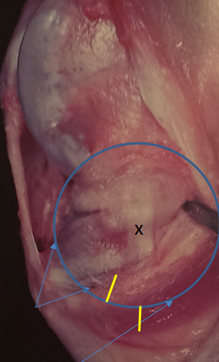

1. Using the TPLO Jig